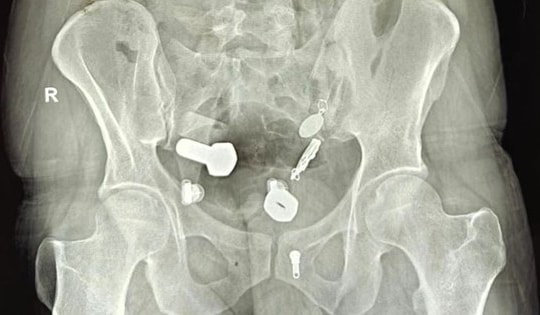

Người đàn ông đau bụng suốt 1 tuần, bác sĩ kiểm tra thì sốc nặng

Sau gần một giờ phẫu thuật, các bác sĩ đã lấy thành công cả hai chiếc thìa ra khỏi bụng người đàn ông.